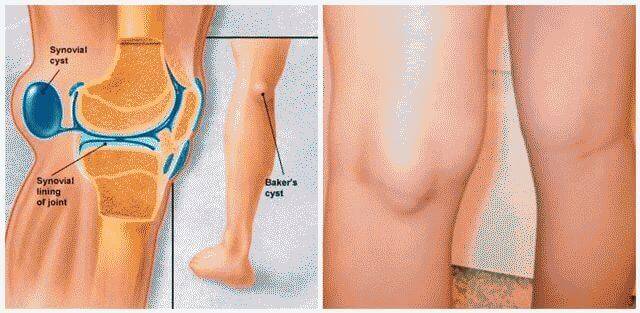

Возможные причины болей в ноге ниже колена и рекомендации